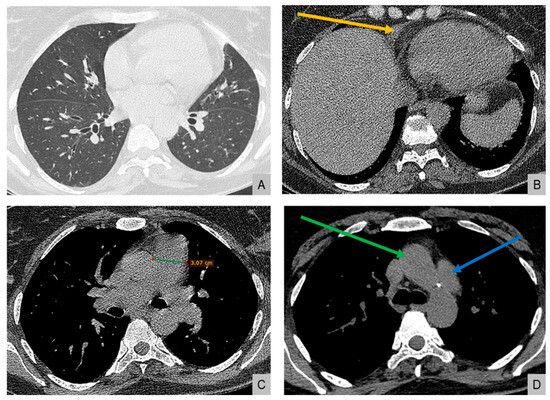

High-resolution computed tomography (HRCT) (Figure 2) showed markedly dilated pulmonary arteries, a small pericardial effusion, and absence of interstitial lung disease or features of pulmonary veno-occlusive disease. The “egg-and-banana sign” was observed (Figure 2D), with the main pulmonary artery appearing enlarged and ovoid (‘egg’) above the aortic arch (‘banana’), a pattern typically seen in pulmonary hypertension.

Figure 2.

High-resolution computed tomography. (A) Normal lung parenchyma. (B) Small pericardial effusion (orange arrow). (C) Dilated main pulmonary artery measuring 30.7 mm (normal <27 mm in females). (D) The “egg-and-banana sign” in pulmonary hypertension: the dilated pulmonary artery (blue arrow, ‘egg’) seen above the lower margin of the aortic arch (green arrow, ‘banana’).